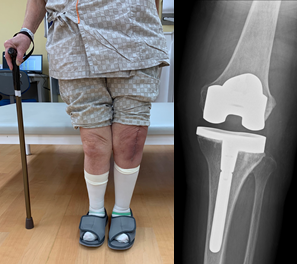

人工膝関節全置換術 (total knee arthroplasty: TKA)

- 末期の変形性膝関節症に対しては、TKAを行います。

患者さんの術前の膝関節可動域や画像所見を十分に検討し、それぞれに適したインプラントおよび術式を選択しています。また、手術精度の向上を目指したコンピュータナビゲーションを2機導入し、より正確な手術の達成や臨床研究のデータ解析に活用しています。 - さらにコンピュータ支援手術の開発を行なっています。